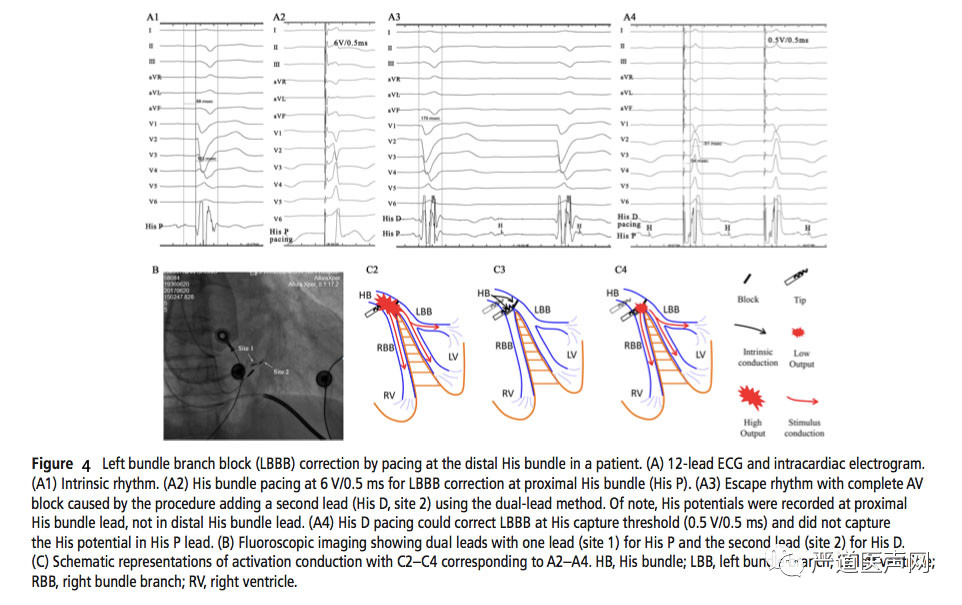

目前纠正近端阻滞的完左机制主要包括:最早的“纵向分离理论”、Dr.Tung的研究“阻滞部位高”以及临床中高电压夺获远端现象。在临床中更容易验证的情况如图3所示,低电压夺获希氏束,相对较高电压纠正LBBB。如图4所示 21.4%患者HBP夺获阈值和纠正阈值都偏低,这提示显示了起搏位点已经接近或超越阻滞点。更深更远跨越阻滞点HBP的植入更好提高LBBB的纠正率,避免并减少阻滞点远端的传导系统病变进展,使得我们选择使用相对较低输出来恢复希浦系统传导,进而使得QRS宽度得到最大程度纠正成为可能。跨过阻滞点进行HBP远端起搏进而纠正束支传导阻滞,因此更深更远的HBP才可能获得较好的起搏和纠正阈值;更深更远的理念才有现今革命性左束支区域起搏(LBBP)的产生和发展,实际上在我们的患者中有6例为LBBP纠正,基线阈值为0.63±0.19mV/0.5ms,而1年随访后参数非常稳定(0.71±0.17mV/0.5 ms)。

图4